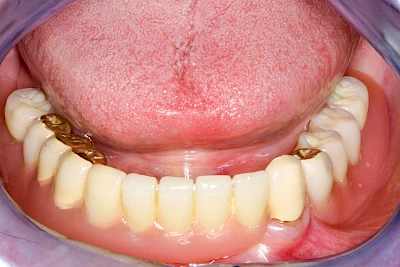

Implantate: Prothesen

Bei herausnehmbaren Prothesen werden Implantate eingesetzt, um den Halt und den Tragekomfort der Prothesen zu verbessern. Dazu kommen verschiedene Verbindungselemente zum Einsatz:

- Teleskope

- Kugelköpfe

- Tellerförmige Lokatoren

- Stege

- Magnete (selten)

Neben rein implantat-getragenen zahnärztlichen Versorgungen werden bei herausnehmbaren Prothesen Implantate auch in Sinne einer "strategischen Pfeilervermehrung" ergänzend zu eigenen Zähnen zur Verankerung eines Zahnersatzes genutzt.

Varianten zur Verankerung von abnehmbarem Zahnersatz auf Implantaten